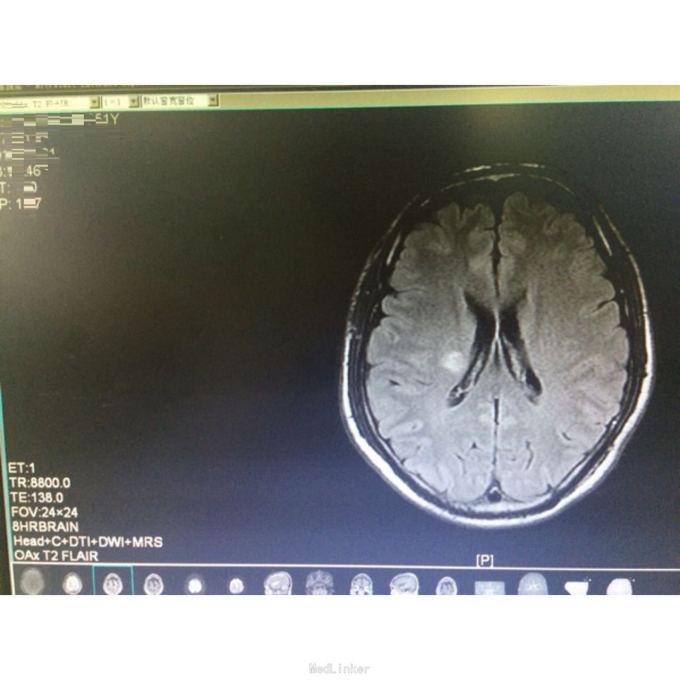

查体:言语清,对答可。左侧肢体肌力5-级,病理征未引出。 辅查:头颅MR示:右侧放射冠、基底节区、颞叶急性脑梗塞。心彩示可疑小孔房缺。锁骨下、颈部血管彩超未见明显异常。血脂正常。

诊断:脑梗死(右侧放射冠、基底节区及颞叶,急性期),高脂血症,房间隔缺损。 予双联抗血小板、克赛、强化他汀、改善循环治疗,辅以针灸、康复锻炼治疗。